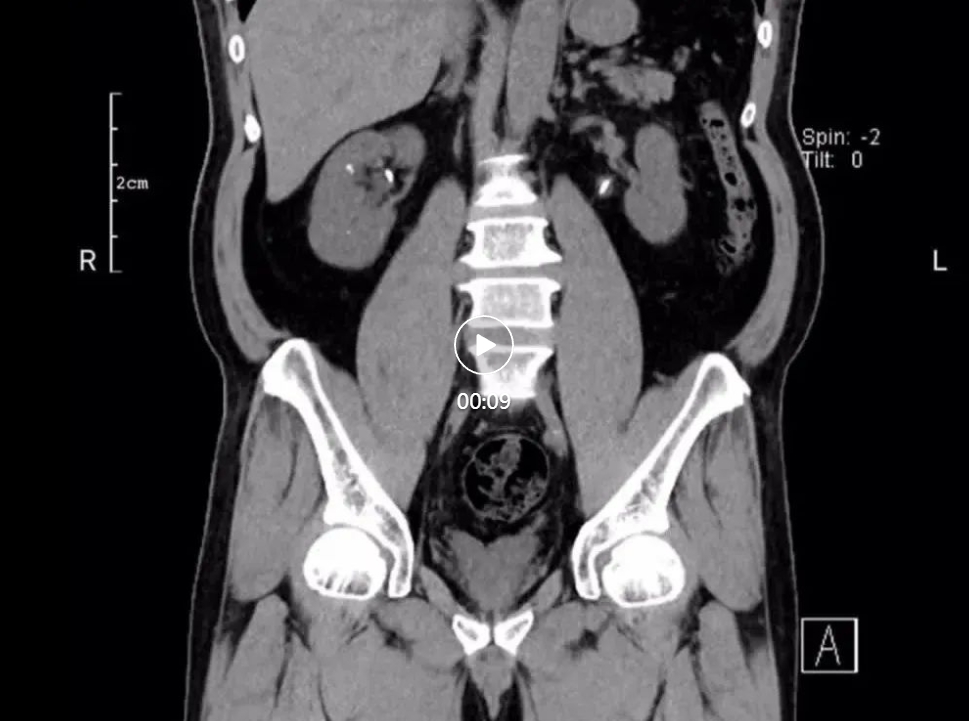

近日,我院成功为一名因双侧输尿管结石完全梗阻,导致急性肾功能衰竭的患者实施“双侧输尿管镜同期手术”,将患者肾功能从崩溃边缘拉回。经过精心治疗,患者肾功能已恢复正常,目前状态良好。60岁的谢先生,因突发右侧腰部绞痛到我院泌尿外科门诊就诊。经检查发现,谢先生双侧输尿管中段结石完全梗阻,这是典型的"石头堵死生命通道"!双肾出现重度积水,已达"红色警戒线"。肾盂扩张超3cm且皮质变薄。同时已发展为急性肾功能衰竭,肌酐值超过526μmol/L(男性正常值:54—106 μmol/L),尿素达18.1mmol/L(成人正常值:2.5—7.1 mmol/L)。

面对复杂的病情,我院泌尿外科副主任雷鸣迅速组织多学科会诊,经过详细讨论,科室团队一直认为,患者双侧输尿管结石和双肾积水是导致急性肾功能衰竭的主要原因,必须尽快手术解除梗阻,恢复肾脏功能。考虑到谢先生的肌酐值太高,为了稳定其内环境,先进行血液透析,再实施手术解除梗阻更妥。经过血液透析,使肌酐值降至300μmol/L,为后续手术争取了宝贵时间。为避免二次创伤,泌尿外科决定采用“双侧输尿管镜同期手术”方案,一次解决双侧梗阻。术前,通过CT三维重建技术精准定位结石位置,并根据透析后患者身体状况评估手术耐受性。术中,雷鸣带领泌尿外科团队为谢先生实施了经尿道输尿管软镜右侧输尿管激光碎石取石+经尿道输尿管硬镜左侧输尿管激光碎石取石术。运用双镜联合技术,超细输尿管硬镜与软镜协同操作,硬镜快速疏通近端梗阻,软镜处理肾盂残留结石;使用钬激光将双侧结石逐层粉末化,并通过负压吸出碎屑,有效避免术后“石街”形成;术后留置双侧双J管,保障输尿管通畅,促进肾功能恢复。